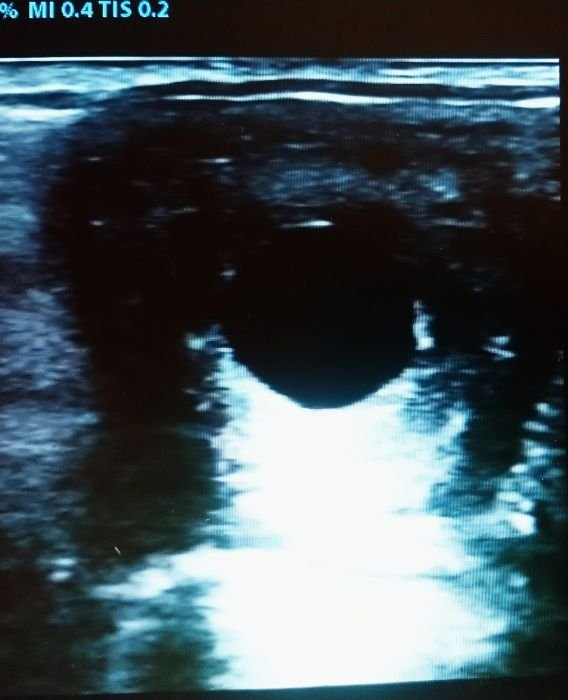

Gravidita klisny 16. den

Pokud nedošlo ke kontrole ovulace, snižuje se šance na zabřeznutí. V době před zjištěním gravidity je vhodné klisnu zbytečně nestresovat, nepřetěžovat. Kontrolu gravidity můžeme provést již 13. den po inseminaci, ideálně 16. den, kdy dochází k uchycení oplozeného vajíčka do děložní sliznice – tzv. nidaci. Další doporučené kontroly jsou cca 35. den a 100.–120. den gravidity. V přibližně 335. den se můžeme těšit na výsledek – dlouho očekávané hříbátko. 🙂